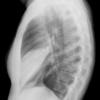

Case 2  Lingular pneum Lat

Date: 04/17/2005

Views: 7421